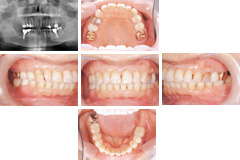

お口全体の健康状態をチェックします。症状のある部分と、全体的な検査も行い、初診時のお口の中の状態を記録いたします。